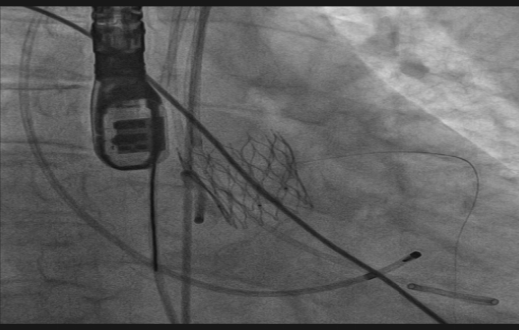

术中,手术团队仅通过患者大腿根部进行微创穿刺,通过血管路径,将人工瓣膜精准输送至心脏病变处并释放,体表几乎不留痕迹。在多学科团队的精密协作与全程护航下,手术顺利完成,术后即刻效果显著。复查心脏彩超显示:原先严重的主动脉瓣狭窄已完全解除,新植入的瓣膜启闭良好,心脏血流恢复通畅。